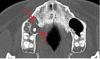

Alexeysvet Опубликовано 24 мая, 2012 Автор Поделиться Опубликовано 24 мая, 2012 (изменено) Подскажите, пожалуйста, правильно ли я читаю, что на фрагменте КТ ниже стрелками указана деструкция стенок гайморовой? Изменено 24 мая, 2012 пользователем Alexeysvet Ссылка на комментарий

ПалСаныч Опубликовано 25 мая, 2012 Поделиться Опубликовано 25 мая, 2012 КТ конечно лучше смотреть на диске. Представленные снимки нечитабельны для стоматолога, ибо не тот баланс яркости/контрастности. Но по тому , что видно, я лично считаю что 16 стоит удалять. Деструкции стенок пазухи нет, это киста в области 16 оттеснила стенку пазухи кверху. Но еще раз, это только предположение, так как всех срезов не видно с нужными дентальными настройками. Ссылка на комментарий

Михалыч007 Опубликовано 25 мая, 2012 Поделиться Опубликовано 25 мая, 2012 Действительно,хотелось бы взглянуть на прицельные сники.Соглашусь с тем,что на 16,скореее всего,есть киста,оттесняющая слизистую гайморовой пазухи.НО!Она(киста)вызвала деструкцию небной кости.Также могу предположить,что киста в обл 15 проросла-таки в пазуху.Ещё в обл 14 зуба на первом снимке(самый крайний нижний левый)-также киста,которая "захватила "половину длины корней.Конечно данных маловато,но если иметь ввиду то что есть,тогда придется удалять и 15 и 16 В процессе удаления 15 скорее всего произойдёт сообщение с пазухой-тогда гайморотомия неминуема.Также обязательно проконсультируйтесь у оториноларинголога.А 14 -если очень повезёт можно срезецировать после лечения каналов,но этот вариант очень-и очень маловероятен-скорее удаление.Однозначно,что данные с КТ на диске намного информативнее.. Ссылка на комментарий